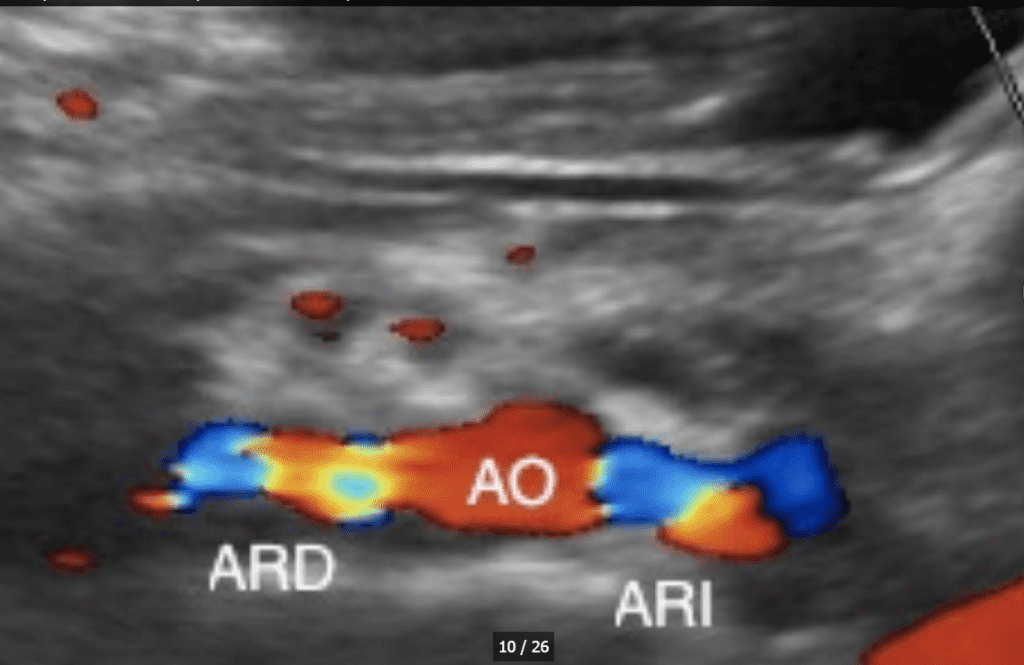

El color doppler imaging o CFM: color flow mapping Codifica la velocidad media del flujo sanguíneo en colores, de acuerdo a una determinada escala, superponiéndola a la imagen Modo B (bidimensional en blanco y negro). La zona de muestreo está determinada por el ROI (caja de color).

El color muestra la dirección del flujo. El del margen superior de la columna siempre representa el flujo hacia el transductor y el contrario el flujo que se aleja del transductor. Mientras mayor sea la velocidad, el color es más brillante.